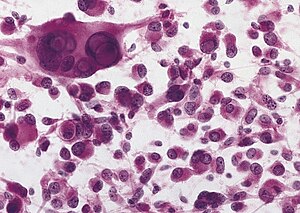

Pleomorphic xanthoastrocytoma. | |

| LM | marked nuclear atypia, eosinophilic granular bodies - very common, inflammation (chronic), no necrosis |

Features:[3]

- Fibrillary background.

- Large cells with marked nuclear atypia.

- Multinuclear cells possible.

- Reticulin meshwork.

- Lipidized cells.

- Eosinophilic granular bodies - very common.[1]

- Inflammatory cells (lymophocytic perivascular cuffs).